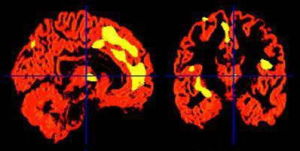

(3).腦ET

(6).單光子反射計算機斷層顯像檢查

利用MED---經顱腦神經遞質檢測技術,區別於傳統單一的檢測方法,整合了FC—腦漲落圖儀、傳統腦神經遞質檢測設備、DNR—多尼爾超導檢測、腦ET、核磁共振、單光子反射計算機斷層顯像等多種檢測手段,利用儀器對人體大腦神經遞質信號的監測,

深層採集人腦三大神經元內標物以及15種中樞神經遞質:包括氮-乙醯天門冬氨酸複合物(N-acetylaspartate,NAA)、膽鹼複合物(Cholin,Cho)和肌酸-磷酸肌酸複合物(Creatin,Cr),以及γ-氨基丁酸(GABA)、谷氨酸(Glu)、5-羥色胺(5-HT)、乙醯膽鹼(Ach)、去甲腎上腺素(NE)、多巴胺(DA)等,充分記錄其功能現狀數據以及綜合活躍程度,同時分析腦部物理損傷及神經元病變參數,並依此製成數位化報告,提交給經驗豐富的精神疾病專家。

濟南五洲醫院精神科再由精神疾病專家根據可視化報告中的腦內神經遞質形態圖譜對患者的病況病狀信息進行科學分析,進而迅速精準的診斷出患者的腦功能活動情況,判斷其病患神經元的位置、受損狀況、還有病變程度,由此結論出患者的病因病灶,確定其治療方法及治療基調。

(2)由於精神疾病的發生與多種腦部疾病有關,以往的CT、核磁共振等檢查技術只能檢測大腦的形態學變化,但多數患者的大腦沒有明顯的形態學方面的改變,因此這就使得臨床心理障礙的治療缺少針對性,導致療效不佳,而MED---經顱腦神經遞質檢測,僅僅需要6分鐘就可以完整採集人體的腦神經遞質信號,並據此建立起配體與受體互相作用的一整套數字依據,在精準定位大腦中受損的腦細胞的同時,迅速診斷出其導致病症的病灶病因,為醫務人員提供腦內神經細胞活動的具體情況,為病症的診斷及治療提供了有效的依據。